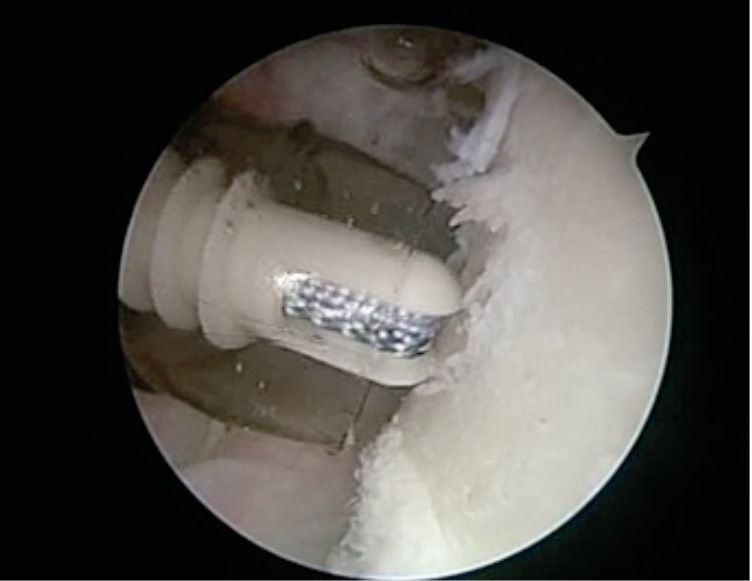

We describe here our technique of performing arthroscopic remplissage. This procedure converts Hill Sach's lesion into an extra-articular structure and acts as a checkrein against anterior translation. Patient is positioned in lateral decubitus. Posterior, antero-inferior and antero-superior portals are made. The antero-superior one is the primary viewing portal and is made more posterior than usual. After adequate viewing of HSL, it is accessed through posterior portal. External rotation of humeral head positions HSL in front of posterior cannula. The bed of the lesion is abraded and an anchor (double or triple loaded) is placed. Putting an anchor in the center of the lesion, closer to the articular surface in mediolateral plane, avoids stiffness in external rotation, post operatively (Figure 9). While passing sutures, posterior cannula should be withdrawn just outside the infraspinatus and beneath the deltoid (Figure 10). Then the sutures are passed using bird beak suture passer, staying lateral to posterior portal avoid stiffness in external rotation. (Figure 11) Then, the knot tying is completed.